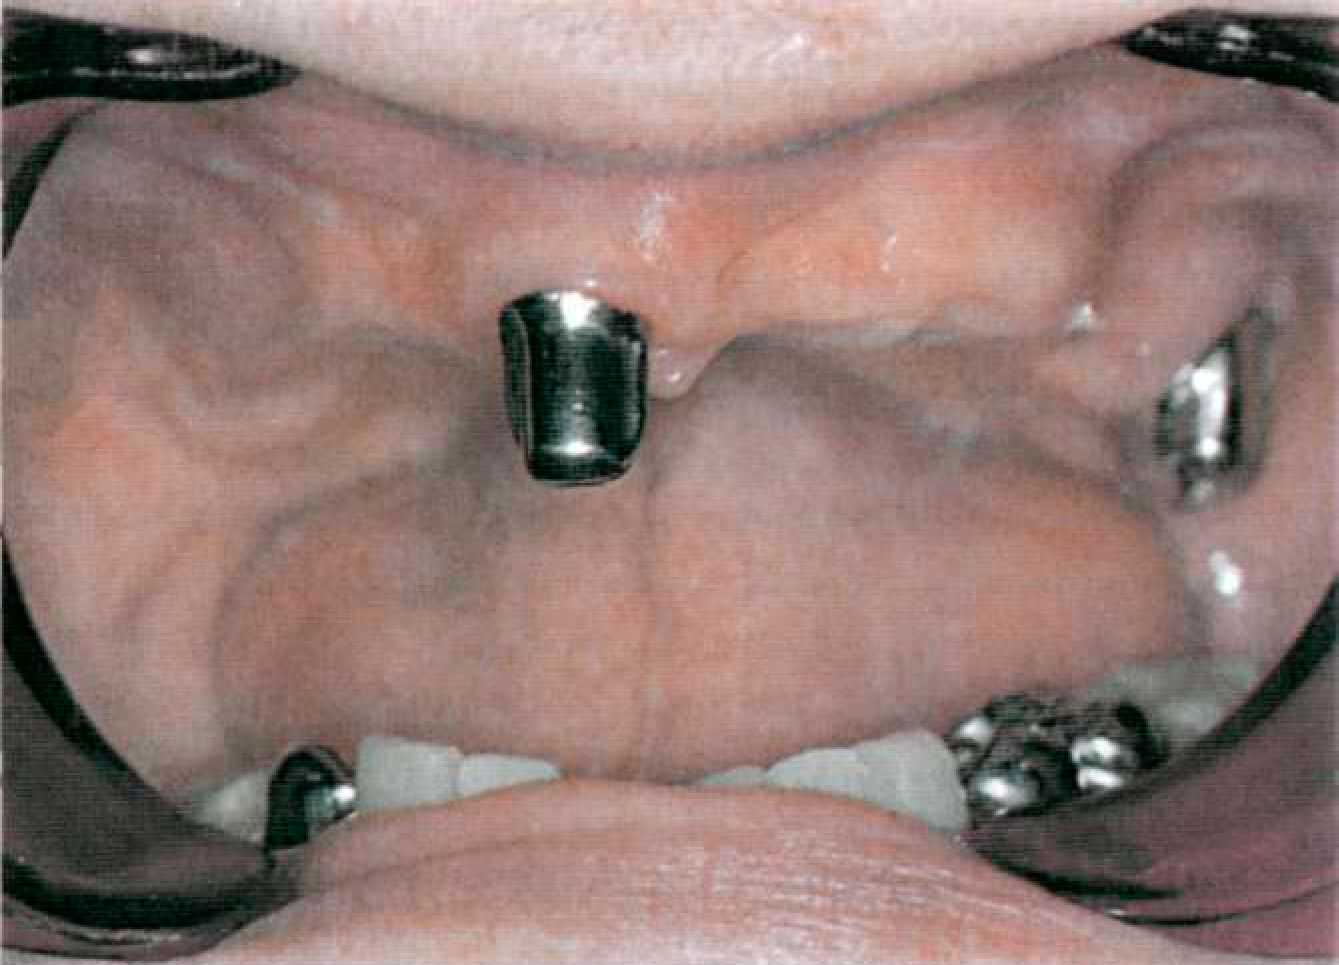

Этап 14. После наложения протеза проводят коррекцию окклюзии и фиксируют первичные коронки на цемент поочередно под контролем покрывного протеза (рис. 144, 145). После фиксации пациента обучают снятию и наложению покрывного протеза, гигиеническим мероприятиям. Уведомляют о необходимости регулярного (каждые 6 месяцев) диспансерного наблюдения у стоматолога. Коррекции базиса покрывного протеза проводят традиционным способом. При необходимости на этапах диспансерного наблюдения проводят перебазировку базиса покрывного протеза. Для этого корригирующим силиконовым оттискным материалом сначала определяют участки атрофии костной ткани. Чаще всего эти участки располагаются по вестибулярной поверхности альвеолярных гребней, так как известно, что наибольшее воздействие оказывают боковые смещения базиса протеза. После этого проводят непосредственно перебазировку (прямым или лабораторным способом).